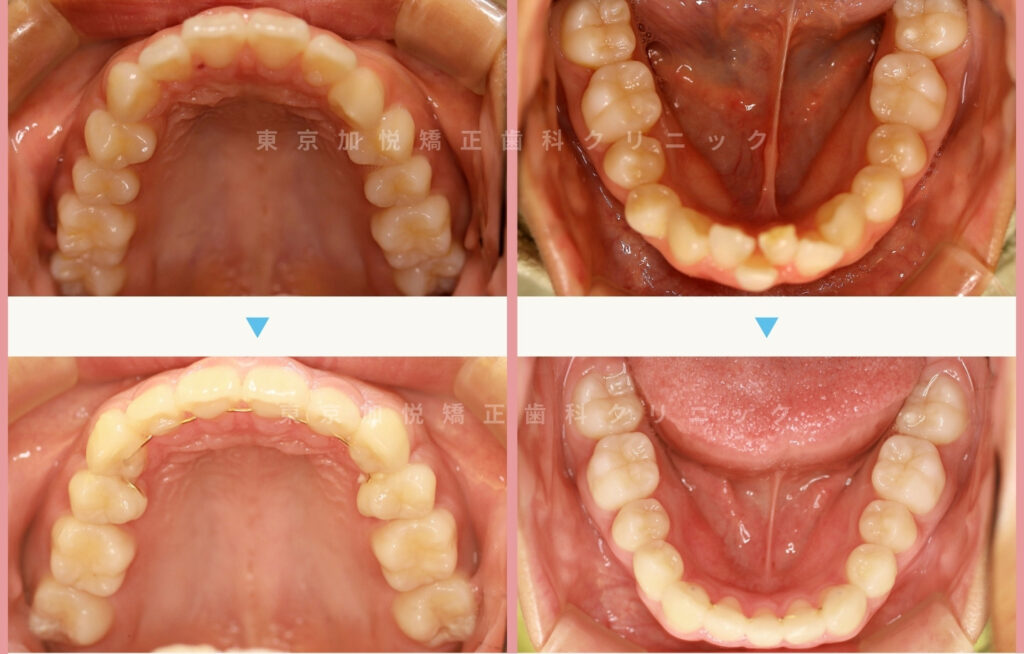

以下は、それぞれの治療前後写真です。

歯を抜いた箇所のすき間もしっかり閉じ、整ったU字の歯列になりました。